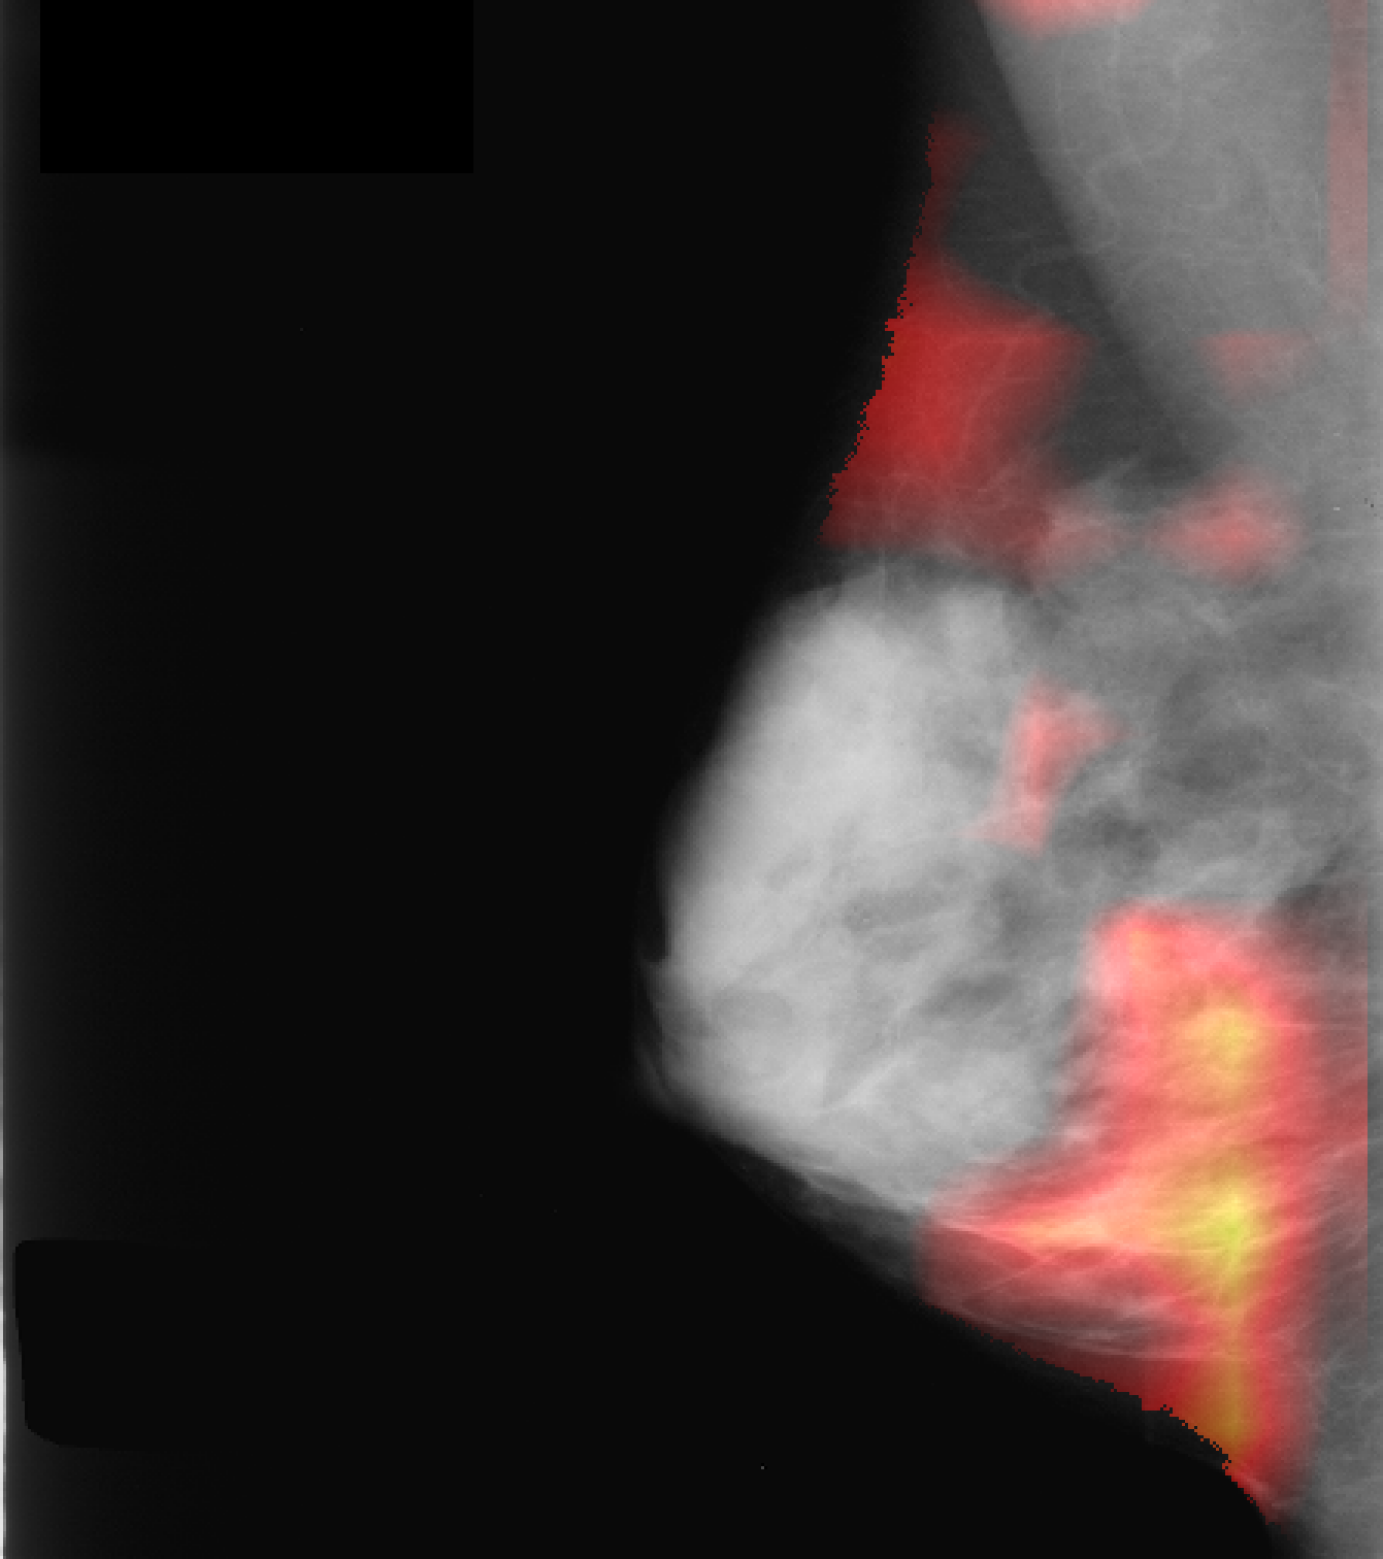

Qualitatively, as depicted in Fig. 3 (b), our salient regions appear at the circumference of masses which is reasonable w.r.t. the fact that this is the discriminative region for the presence of masses. This is in line with [16], which reports on injection of poorly circumscribed, malignant looking masses while transforming healthy cases into pathological ones using a GAN variant. In addition, our method yields more accurate visualizations than CAM and SAL (Fig. 3 first row), i.e. it has a smaller, more precise and more informative feature attribution than these standard visualization methods (Fig. 3 (b)-(d)).